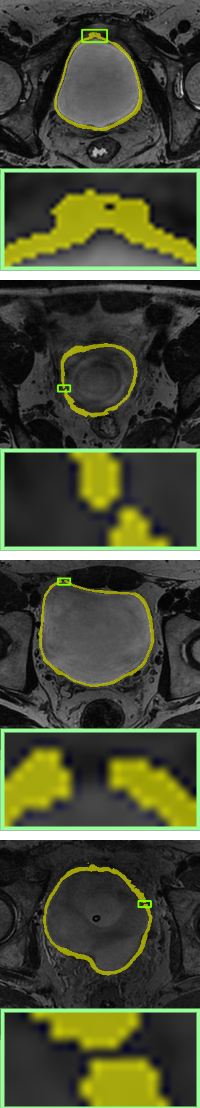

Ground-truth

Without-topo

PH[ph]

Proposed WT

We compare the results of no topological constraints (without-topo), topological constraints without width (PH), and width-aware topological constraints (WT) applied to a number of data-driven models for relevant applications. As can be seen in Table 3, our proposed method (rows with gray background) shows superior performance. Specifically, the improvements in volumetric demonstrate that our method has more accurate result in a pixel-level sense, while the improvements on topology-based metrics demonstrate that WT energy has an overall more precise prediction and topological similarity. For boundary-based indicators, WT performs better compared to PH in most cases due to the width information. The corresponding visualization is given in Fig. 10 and Fig. 11. From the visualization results, it can be seen that in data-driven image segmentation models, no topological constraints will produce obvious topological errors, even if its segmentation results have high accuracy. When constraining topological consistency using persistent homology methods, it may be possible to connect very thin lines to ensure connectivity or a consistent number of holes. We improve the PH method by smoothing the critical points in there structuring elements neighborhood, which can preserve the width information while constraining the topological properties to be consistent.